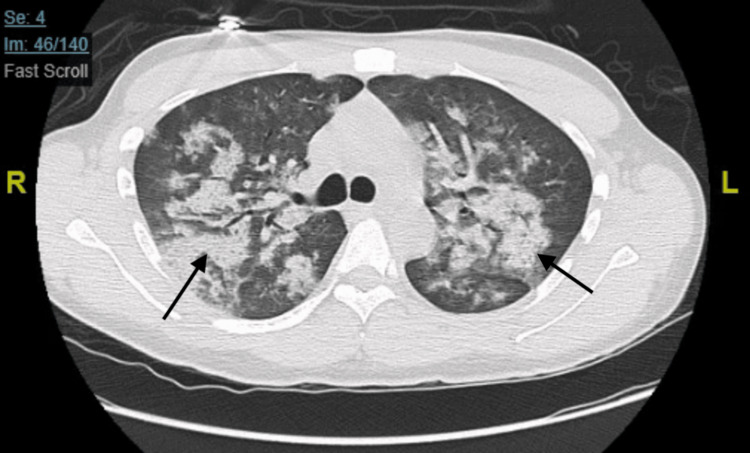

This was followed by a CT scan with contrast, which showed multiple ground-glass opacities present throughout both lungs (Figure 2).